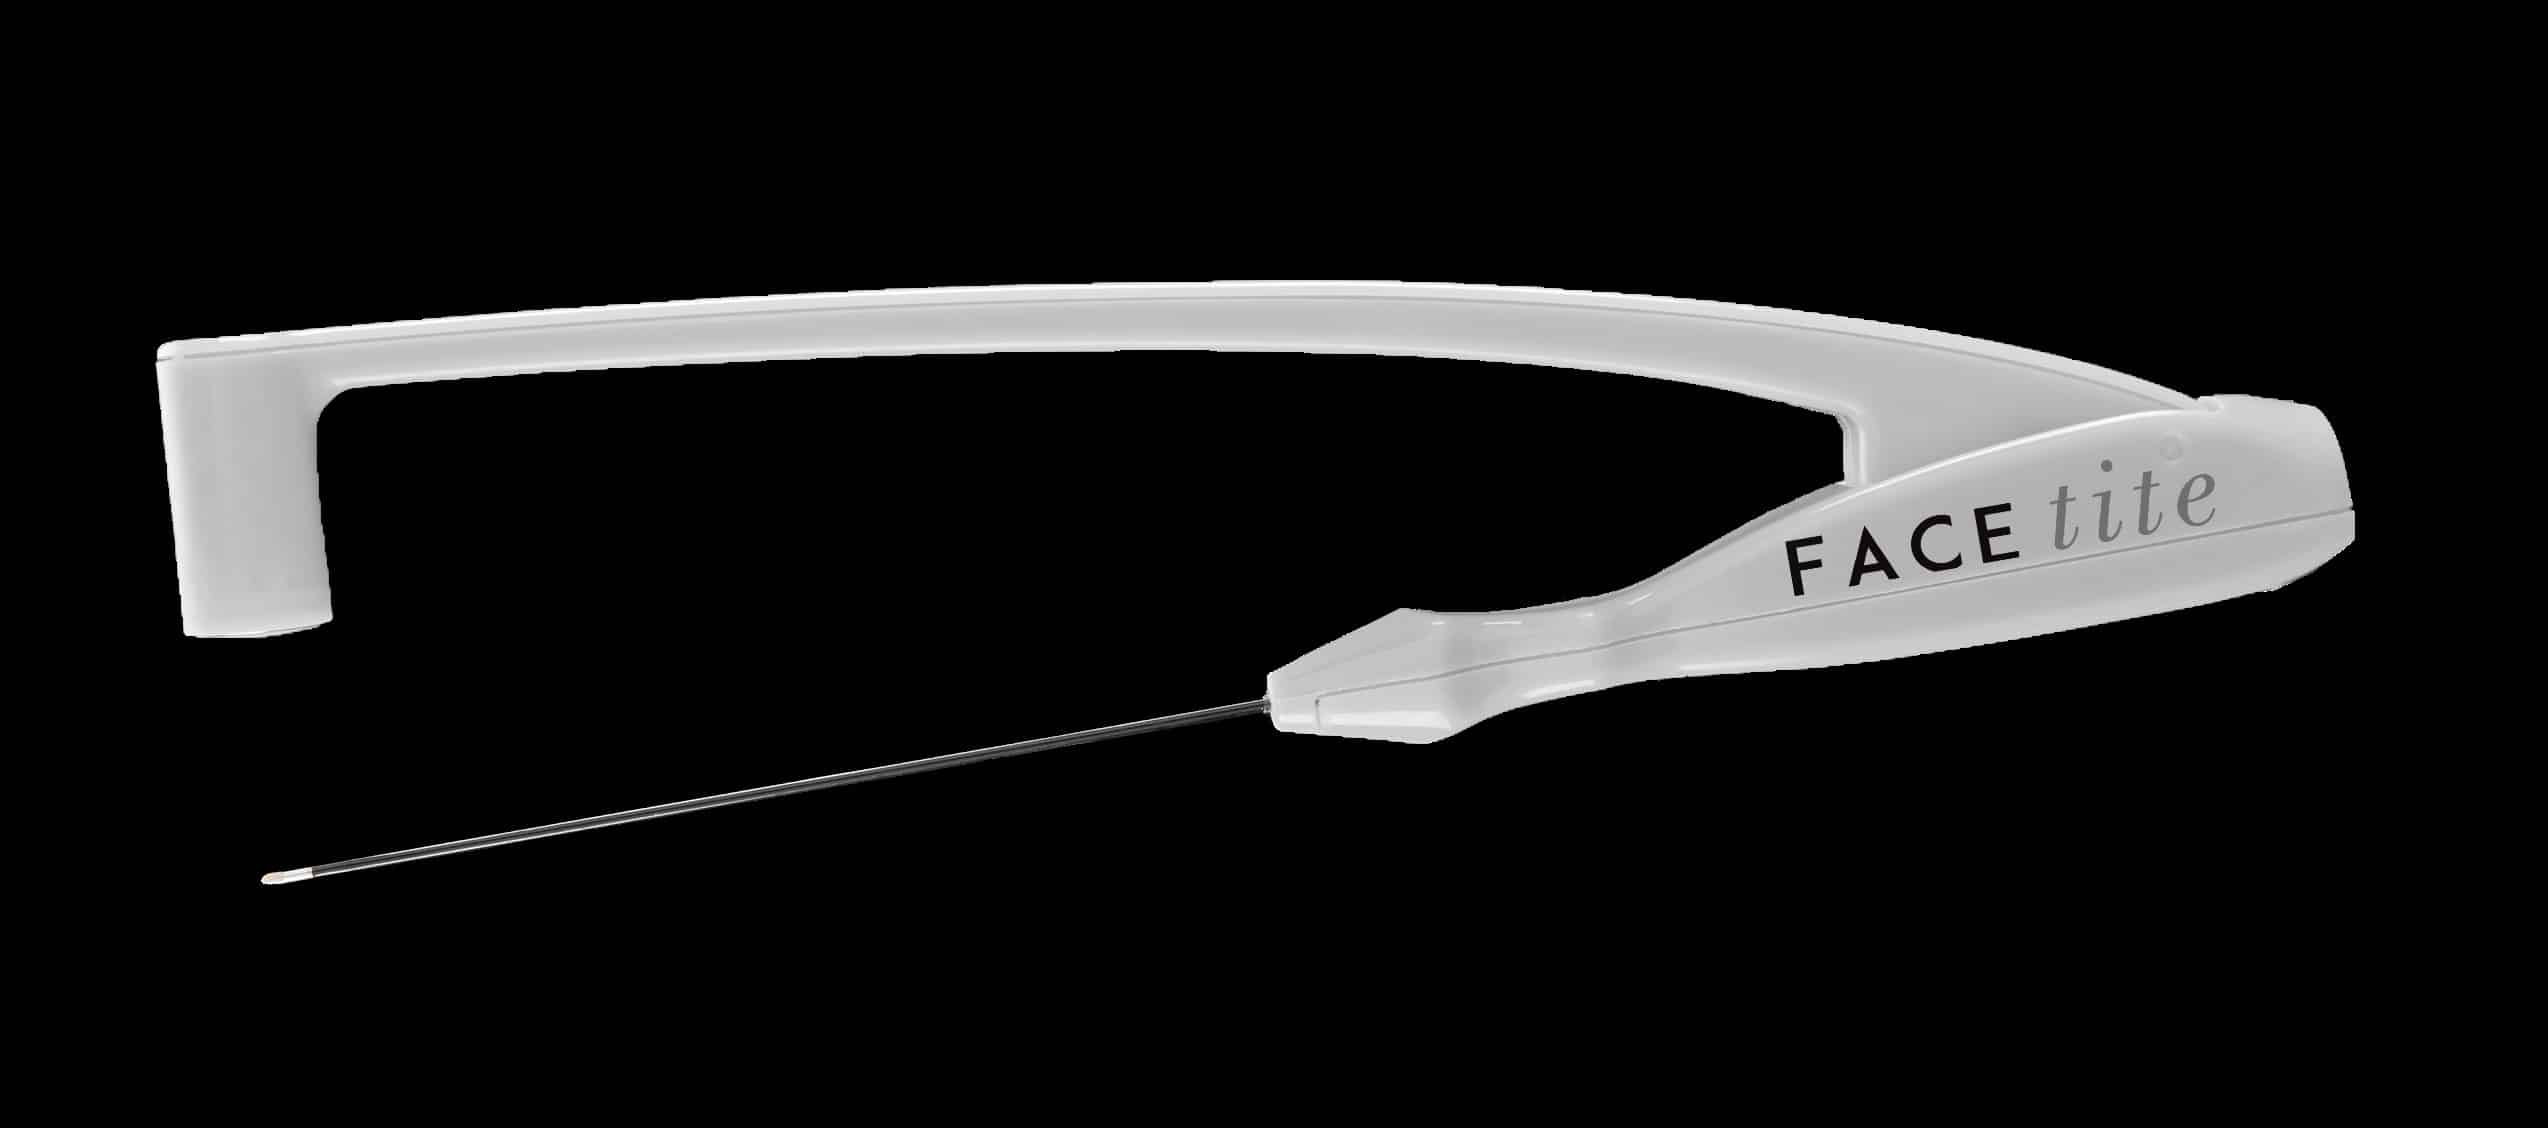

El tratamiento se realiza utilizando una cánula con dos partes: la más fina se introduce en la piel a través de una incisión mínima, mientras que la más gruesa se coloca encima de la piel.

Ambas cánulas cuentan con un electrodo situado en el extremo proximal a través del cual, y de forma bidireccional, se transmiten las ondas de radiofrecuencia produciendo un calentamiento bipolar, rápido y uniforme de la grasa hasta licuarla.

La radiofrecuencia Bodytite también puede aplicarse en la cara y en el cuello para tratar la flacidez y las arrugas.

No te pierdas este artículos sobre Facetite, el lifting facial sin cirugía:

FaceTite: La revolución del lifting facial sin cirugía